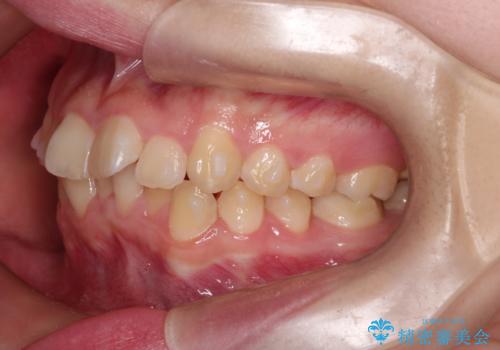

上下の前歯のガタガタを目立たず治したい インビザラインによる見えない矯正

- 上下の前歯のガタガタを治したいとのことで来院されました。

上下の歯と歯の間をわずかに削り、並べる計画としました。

受験生ということもあり、来院頻度が少ないマウスピース矯正で治療が終了できたことに満足いただけました。

上下の正中が一致していませんが、受験を控えているためご本人の希望もあり、いったん終了とさせていただきました。